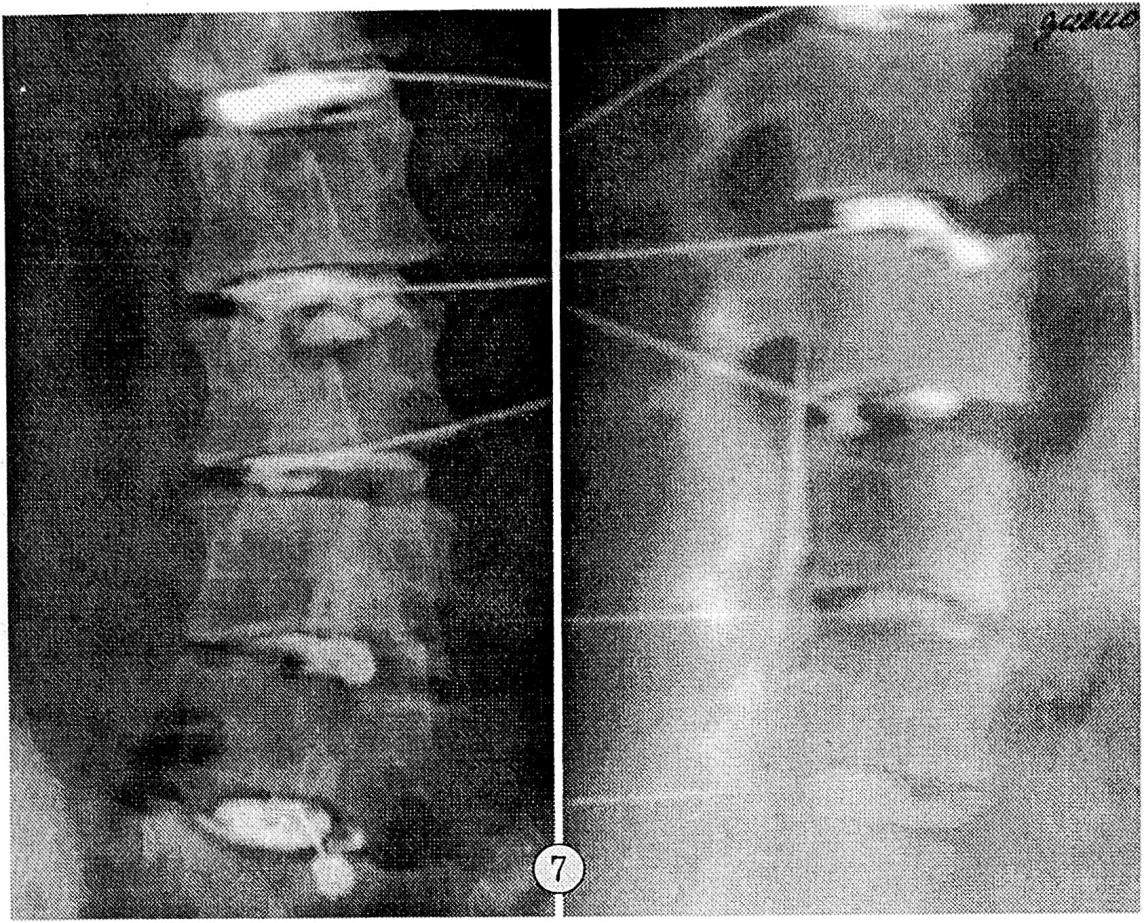

Все варианты дискограмм, относящиеся к чрездисковому типу расположения контрастного вещества, являлись специфическими для поясничной остеохондропатии и отражали диффузную дегенерацию межпозвонкового диска (см. рис. 7).

Рис. 7. Диффузная дегенерация межпозвонковых дисков при поясничной остеохондропатии.

Внеламинарный тип дискограмм наблюдался в сегментах, где имело место отделение переднего апофиза от тела позвонка, и характеризовался выпадением студенистого ядра диска между несросшимся передневерхним апофизом и передневерхним углом тела позвонка. Нуклеарная тень представляла собой протянувшуюся вдоль краниальной поверхности тела позвонка гомогенную полосу шириной 2— 3 мм. В 8 случаях отмечалось контрастирование фрагментов фиброзного кольца. Высота межтелового промежутка оказалась сниженной практически на всех дискограммах (см. рис. 8). Емкость диска составляла не менее 1,5—1,8 мл; введение контрастного вещества не сопровождалось появлением боли.

Рис. 8. Внеламинарный тип дискограмм сегментах L3—4, L4—5.